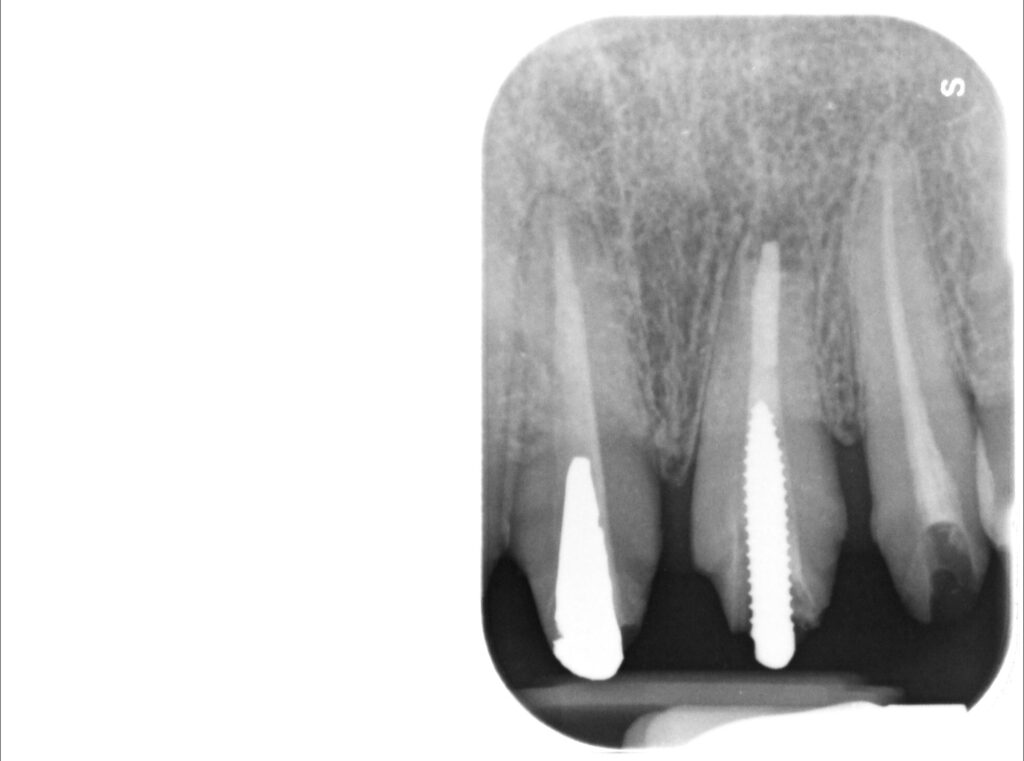

Caso clinico – ritrattamento ortogrado con apical plug in MTA